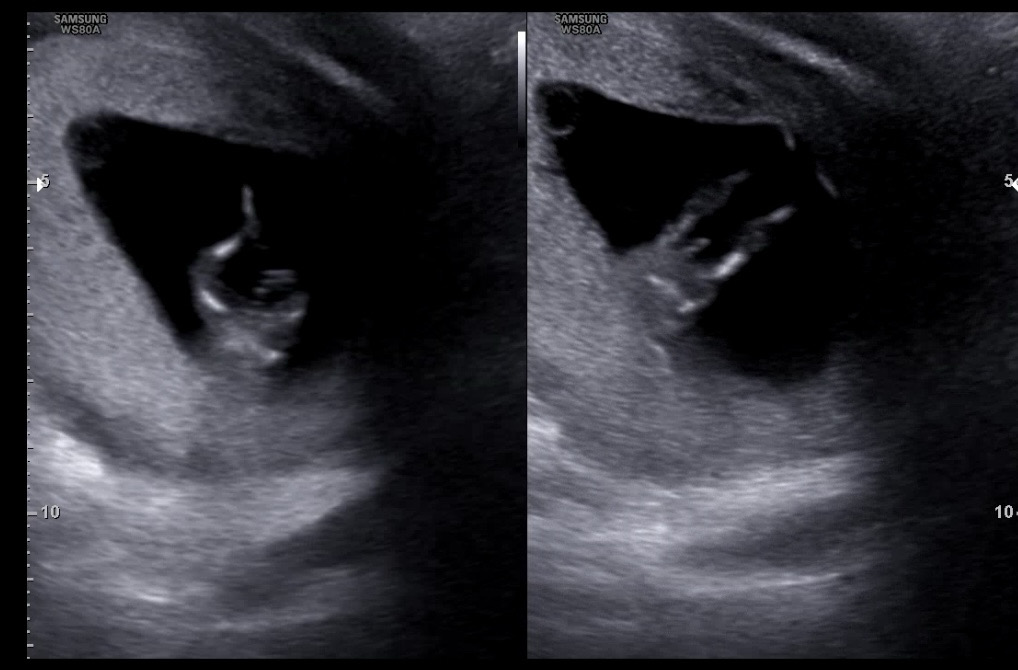

12주에 이정도면 딸일 확률은 없겠죠..?

12주에 다리 사이에 이정도면 딸일수가 없겠죠..? 반전 있으셨던 분 계신가요??

탯줄같아요ㅎㅎ 그리고 12주면 몰라요ㅠ

저정도 길이면 탯줄 아닐까요??

아 그런가요??? 초음파실 선생님이 존재감이 크다하셨는데...

오우... 저도 오늘 초음파 보고왔는데(12주차) 저한테는 탯줄이니 걱정말라고 하셨거든요 그래서 탯줄 아닐까 했는데..!